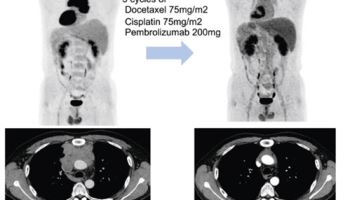

70세 넘은 3기 폐암 환자도 ‘적극적 치료’ 가능